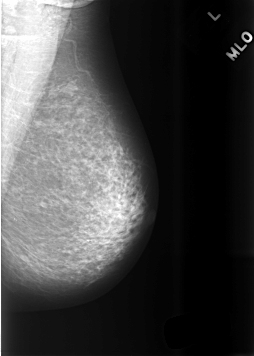

C_0475_1.LEFT_MLO

LEFT_MLO LINES 5696 PIXELS_PER_LINE 4064 BITS_PER_PIXEL 12 RESOLUTION 50 NON_OVERLAY